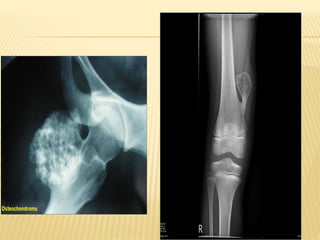

OSTEOCHONDROMA

 Also known as: Osteocartilaginous Exostosis

 Cartilage capped bony projection on external

surface of bone containing a marrow cavity that

is continuous with underlying bone

 Commonest benign tumour of bone.

 Lesion has its own growth plate, usually stops

X RAY

 Pedunculated / sessile – exophytic

 metaphysis / diaphysis

 Marrow and cortices of lesion continuous with

bone

 Directed away from growing end

 Cartilage cap not seen on x ray